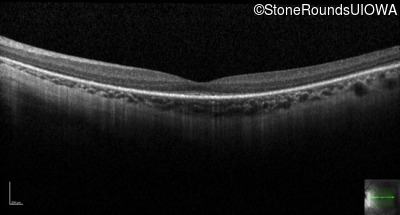

Age at visit: 16 years